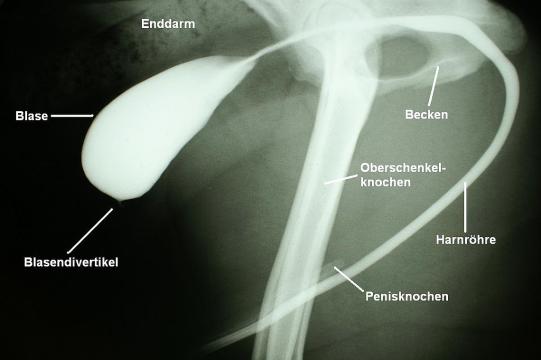

Aus der nun leicht gefüllten Blase wird mittels Punktion Urin entnommen. Mikroskopisch sind darin Blut und Entzündungszellen zu finden, der bakteriologische Untersuch verläuft aber negativ. Unter leichter Sedation wird eine Kontrastuntersuchung der Harnröhre durchgeführt. So könnten mögliche Hindernisse (Steine, Gewebszubildungen) erkannt werden.

Die Studie zeigt, dass die Harnröhre keinerlei Verengungen aufweist. Hingegen ist am vorderen Blasenpol eine kleine, mit Kontrastmittel gefüllte Ausstülpung zu erkennen: ein sogenanntes Blasen- oder Urachusdivertikel! Da diese kleine Ausstülpung nicht oder nur schlecht mit antibiotikumhaltigem Urin in Kontakt kommt, ist hier ein Überleben von Bakterien trotz Antibiose möglich, was das Fortbestehen von Symptomen erklären könnte.